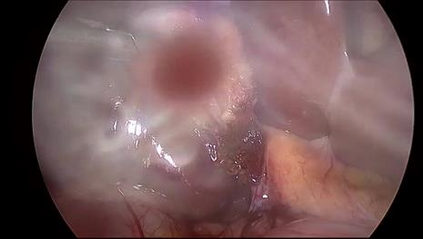

Anomaly detection in Minimally-Invasive Surgery (MIS) traditionally requires a human expert monitoring the procedure from a console. Data scarcity, on the other hand, hinders what would be a desirable migration towards autonomous robotic-assisted surgical systems. Automated anomaly detection systems in this area typically rely on classical supervised learning. Anomalous events in a surgical setting, however, are rare, making it difficult to capture data to train a detection model in a supervised fashion. In this work we thus propose an unsupervised approach to anomaly detection for robotic-assisted surgery based on deep residual autoencoders. The idea is to make the autoencoder learn the 'normal' distribution of the data and detect abnormal events deviating from this distribution by measuring the reconstruction error. The model is trained and validated upon both the publicly available Cholec80 dataset, provided with extra annotation, and on a set of videos captured on procedures using artificial anatomies ('phantoms') produced as part of the Smart Autonomous Robotic Assistant Surgeon (SARAS) project. The system achieves recall and precision equal to 78.4%, 91.5%, respectively, on Cholec80 and of 95.6%, 88.1% on the SARAS phantom dataset. The end-to-end system was developed and deployed as part of the SARAS demonstration platform for real-time anomaly detection with a processing time of about 25 ms per frame.